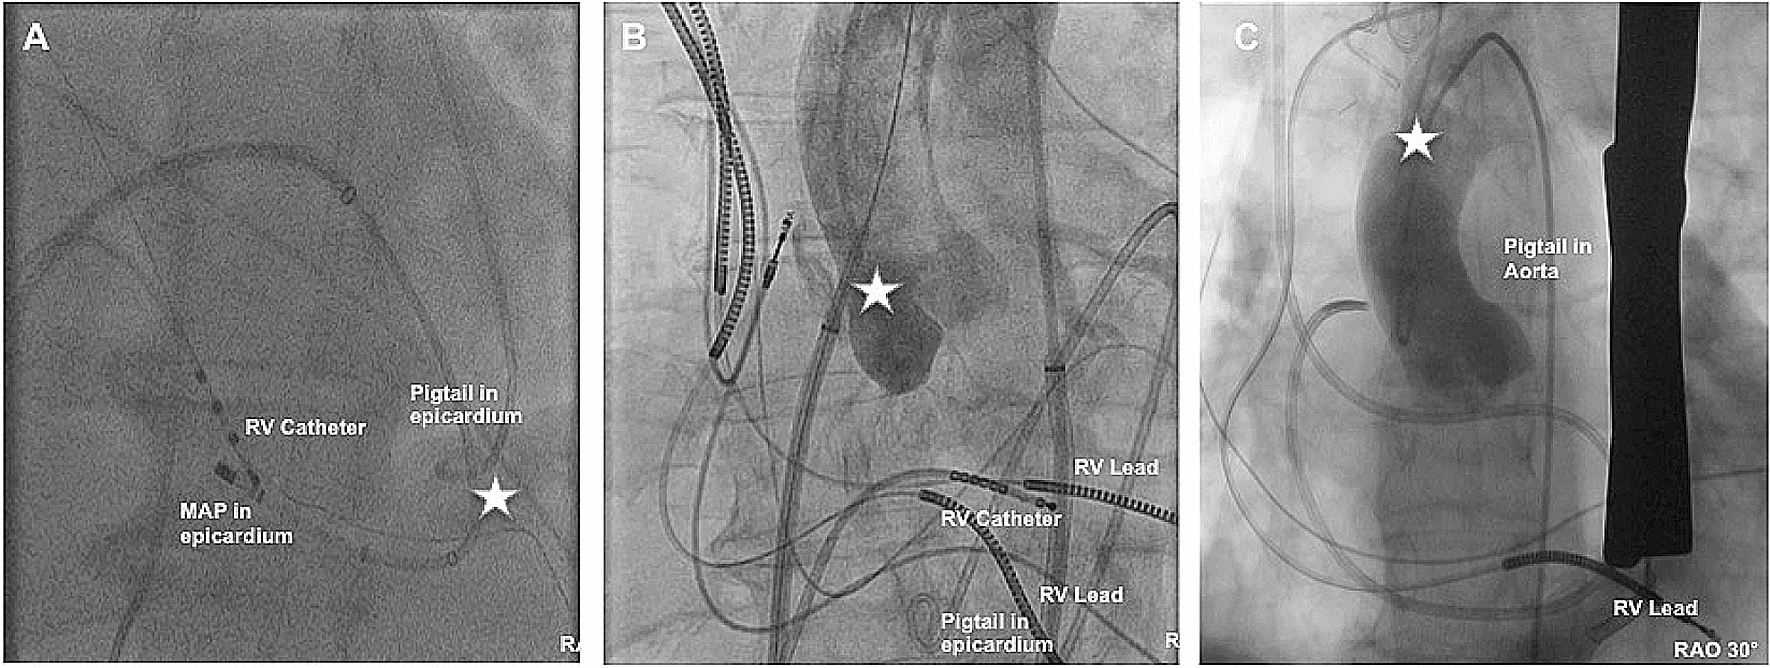

a, b Inferior epicardial access with fluoroscopy projection in AP. White arrows in b illustrate the contrast media within the pericardial space. c, d Anterior epicardial access with fluoroscopy projection in LAO 90°. Yellow dotted line illustrates the silhouette of the heart. Red dotted line illustrates the triangle between sternum, abdominal organs and heart. With permission of the Institute of Pathology, Asklepios Hospital St. George. LAO Left anterior oblique, AP Anteroposterior, RV right ventricle

Fig. 3

a Shows an apical LV perforation. The distal Ablation catheter is located epicardially. b Shows an accidental puncture of the aorta during transseptal puncture. The dilator is located in the aorta. c Shows an angiography after successful cardiac surgery due to perforation of the aorta ascendens via the distal sharp end of the SL1 Sheath. Star marks the perforation side. RAO Right anterior oblique, RV right ventricle, MAP Ablation catheter